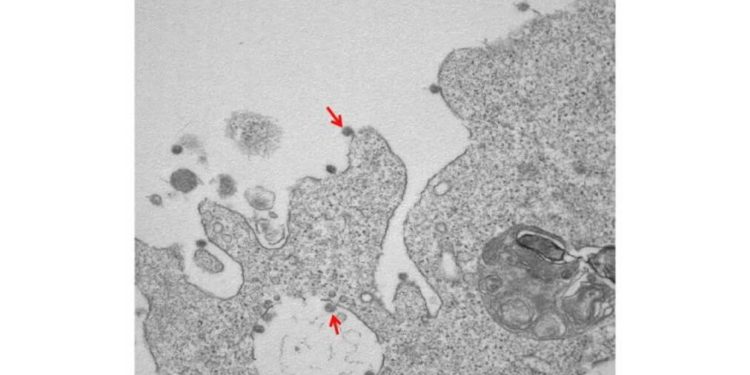

Foto Coronavirus 'lombardo': ricercatori della Statale di Milano isolano il ceppo all'ospedale Sacco, ecco l'immagine in bianco e nero da microscopio.

Foto in bianco e nero con corona: purtroppo non si tratta di un ritratto di qualche regnante di fine Ottocento-inizio Novecento, bensì di una immagine del Coronavirus. Un successo comunque per la scienza, sono infatti le prime foto del Coronavirus ‘lombardo’, per merito dei ricercatori dell’Università degli Studi di Milano, la Statale del capoluogo lombardo.

Sono state dunque catturate al microscopio elettronico le prime immagini del virus Sars-CoV-2 isolato nel Laboratorio di Malattie infettive dell’Università Statale-ospedale Luigi Sacco, coordinato da Massimo Galli e Gianguglielmo Zehender, in collaborazione con l’Anatomia patologica diretta da Manuela Nebuloni del Dipartimento di Scienze biomediche e cliniche Luigi Sacco.

Hanno ottenuto gli isolamenti quattro ricercatori di UniMi: si tratta di Alessia Lai, Annalisa Bergna, Arianna Gabrieli (tre giovani scienziate precarie) e di Maciej Tarkowski, ricercatore polacco in forze alla Statale di Milano, mentre hanno effettuato le osservazioni al microscopio elettronico e prodotto le immagini Antonella Tosoni e Beatrice Marchini.

In una fotografia, spiegano dall’ateneo, “si osservano chiaramente, ad un ingrandimento di 30000X, le particelle virali di Sars-CoV-2, adese alle membrane sulla superficie e all’interno di cellule Vero E6 utilizzate per l’isolamento”. Una seconda foto è invece “la combinazione di 2 immagini a diverso ingrandimento (50000X e 140000X) che mostra le particelle virali con la tipica ultrastruttura caratterizzata dalla corona di glicoproteine superficiali”.

Lo studio, pubblicato nel Journal of Medical Virology, è basato sull’isolamento e la caratterizzazione dei genomi virali di tre pazienti appartenenti al primo gruppo di 16 casi di Covid-19 provenienti dalla provincia di Lodi. Qui entrambe le foto (da TgCom24).